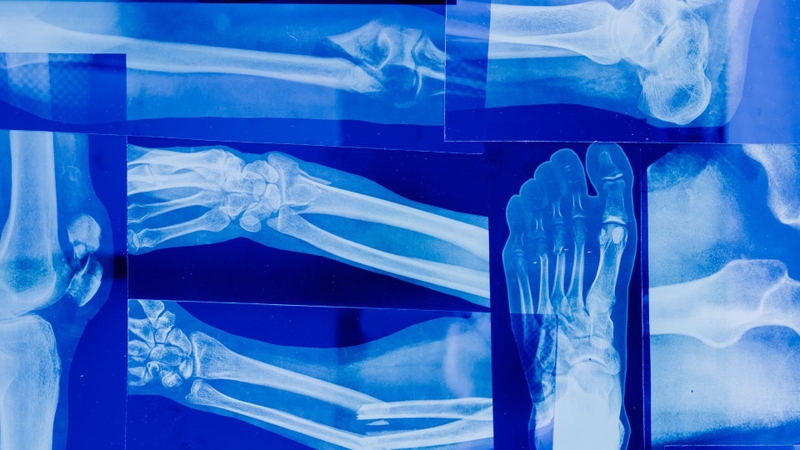

Khả năng xuyên thấu của tia X và ứng dụng trong điều trị ung thư 1

Khả năng xuyên thấu của tia X nhờ nguồn bức xạ năng lượng cao

Cụ thể, các mô có mật độ cao như xương sẽ hấp thụ tia X nhiều hơn so với các mô mềm như cơ và mô mỡ. Điều này tạo ra sự khác biệt về độ sáng trên phim X-quang, giúp bác sĩ có thể phân biệt được các loại mô và cấu trúc trong cơ thể.

Khả năng xuyên thấu của tia X là yếu tố quan trọng trong việc chẩn đoán bệnh lý. Khi tia X đi qua cơ thể, chúng tạo ra hình ảnh về các bộ phận bên trong cơ thể, giúp phát hiện các khối u, viêm nhiễm, hay các bất thường khác trong cơ thể. Đây là lý do tại sao tia X đã trở thành một công cụ chẩn đoán quan trọng trong y học.